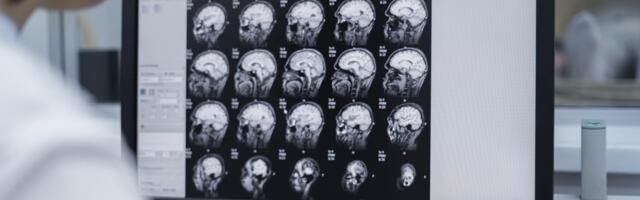

Danish medtech company Brainreader has raised €6.6 million to accelerate the global rollout of its AI-driven diagnostic platform Neuroreader. Neuroreader is a CE-marked and FDA-cleared software platfo...